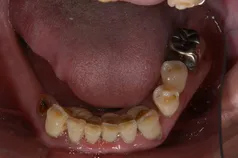

[症例1]

重度の歯周病で奥歯がすでになくなっており、そのため前歯もグラグラの状態でした。

右上の前歯(向かって左上)は自然に抜け落ちたそうです。

下の前歯の裏側には多量の歯石がたまっています。

【処置内容】

歯周初期治療、全体に歯周外科処置を実施、その後セラミックブリッジ、セラミッククラウン、

右上6・5番、左上3・4・5・6番、左下6番、右下4・6番にインプラントを実施。

• 治療期間:約2年

• 治療費:400万円

• 治療回数:30回